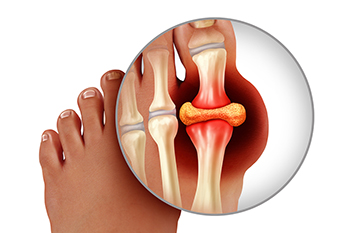

Why Does Gout Affect the Big Toe?

Gout is a type of arthritis caused by a buildup of uric acid in the bloodstream. This uric acid can crystallize in the joints, leading to symptoms such as sudden and severe pain, swelling, stiffness, redness, and warmth in the affected joint. While a gout flare up can hit any joint in the body, it is most frequently found at the base of the big toe joint. Because uric acid is sensitive to temperature changes, it crystallizes when temperatures are cooler. Because the big toe is the furthest part of the body from the heart, it is also the coolest part of the body. This creates the perfect environment for uric acid to crystallize and for a gout attack to occur. If you experience painful gout flare ups in your feet, it is suggested that you consult with a podiatrist.

Gout is a type of arthritis caused by a buildup of uric acid in the bloodstream. It often develops in the foot, especially the big toe area, although it can manifest in other parts of the body as well. Gout can make walking and standing very painful and is especially common in diabetics and the obese.

Gout can easily be identified by redness and inflammation of the big toe and the surrounding areas of the foot. Other symptoms include extreme fatigue, joint pain, and running high fevers. Sometimes corticosteroid drugs can be prescribed to treat gout, but the best way to combat this disease is to get more exercise and eat a better diet.

Everything You Need to Know About Gout

Gout, typically found in diabetic patients, is an unusually painful form of arthritis caused by elevated levels of uric acid in the bloodstream. The condition typically strikes the big joint on the big toe. It has also been known to strike the knees, elbows, fingers, ankles and wrists—generally anywhere that has a functioning, moving joint.

The high level of uric acid in a person’s bloodstream creates the condition known as hyperuricema—the main cause of gout. Genetic predisposition occurs in nine out of ten sufferers. The children of parents who suffer gout will have a two in ten chance of developing the condition as well.

This form of arthritis, being particularly painful, is the leftover uric acid crystallizing in the blood stream. The crystallized uric acid then travels to the space between joints where they rub, causing friction when the patient moves. Symptoms include: pain, redness, swelling, and inflammation. Additional side effects may include fatigue and fever, although reports of these effects are very rare. Some patients have reported that pain may intensify when the temperature drops, such as when you sleep.

Most cases of gout are easily diagnosed by a podiatrist’s assessment of the various symptoms. Defined tests can also be performed. A blood test to detect elevated levels of uric acid is often used as well as an x-ray to diagnose visible and chronic gout.

Treatment for gout simply means eliminating symptoms. Non-steroid anti-inflammatory drugs or NSAIDs (Colchicine and other corticosteroid drugs, etc.) will quell the redness, the swelling, and the inflammation. However, managing your diet, lifestyle changes, and using preventative drugs are all helpful toward fully combating the most severe cases.